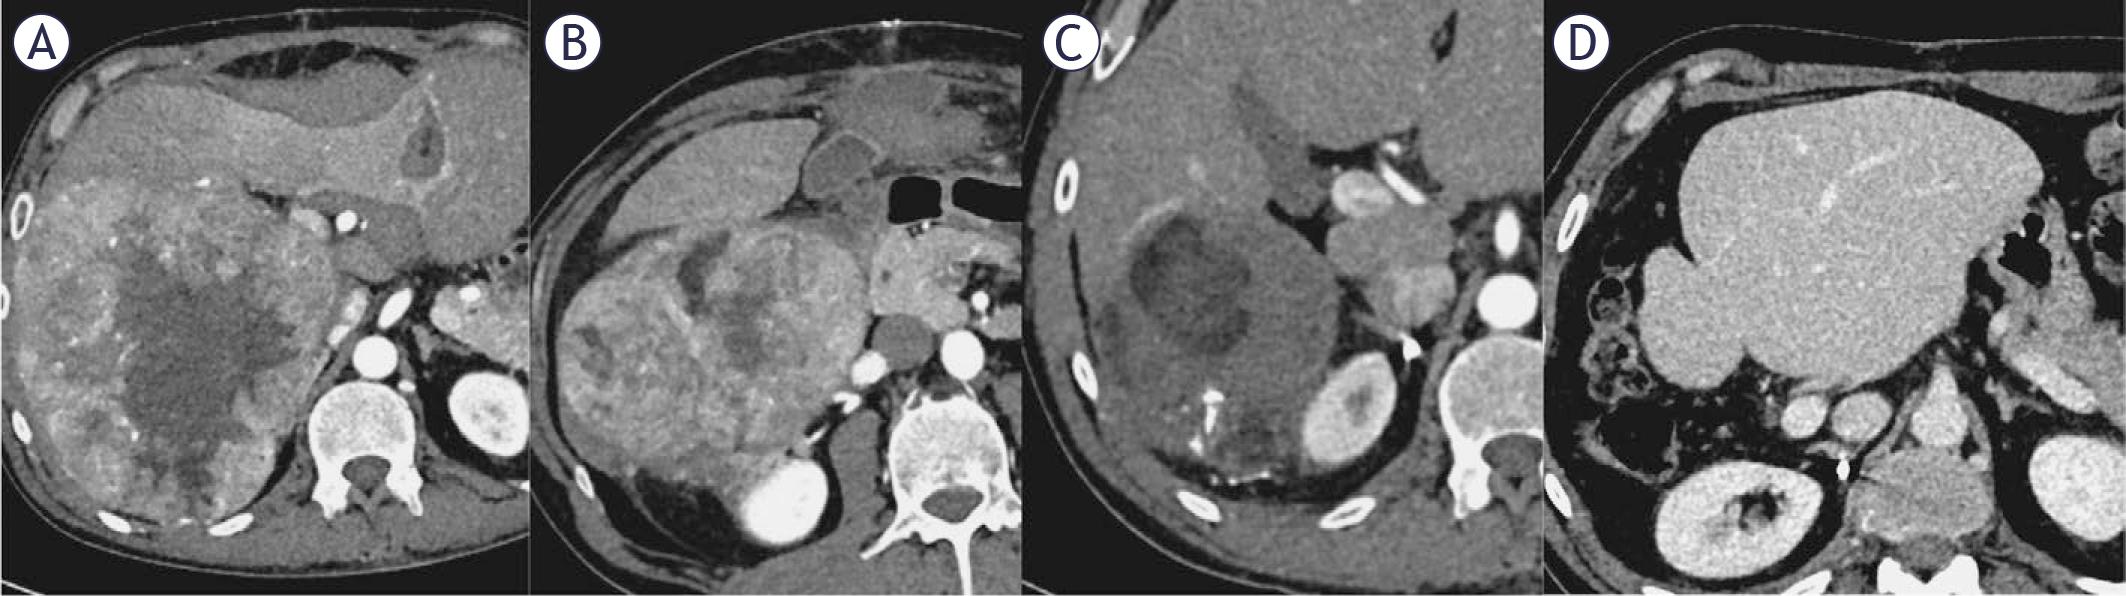

FIGURE 3.